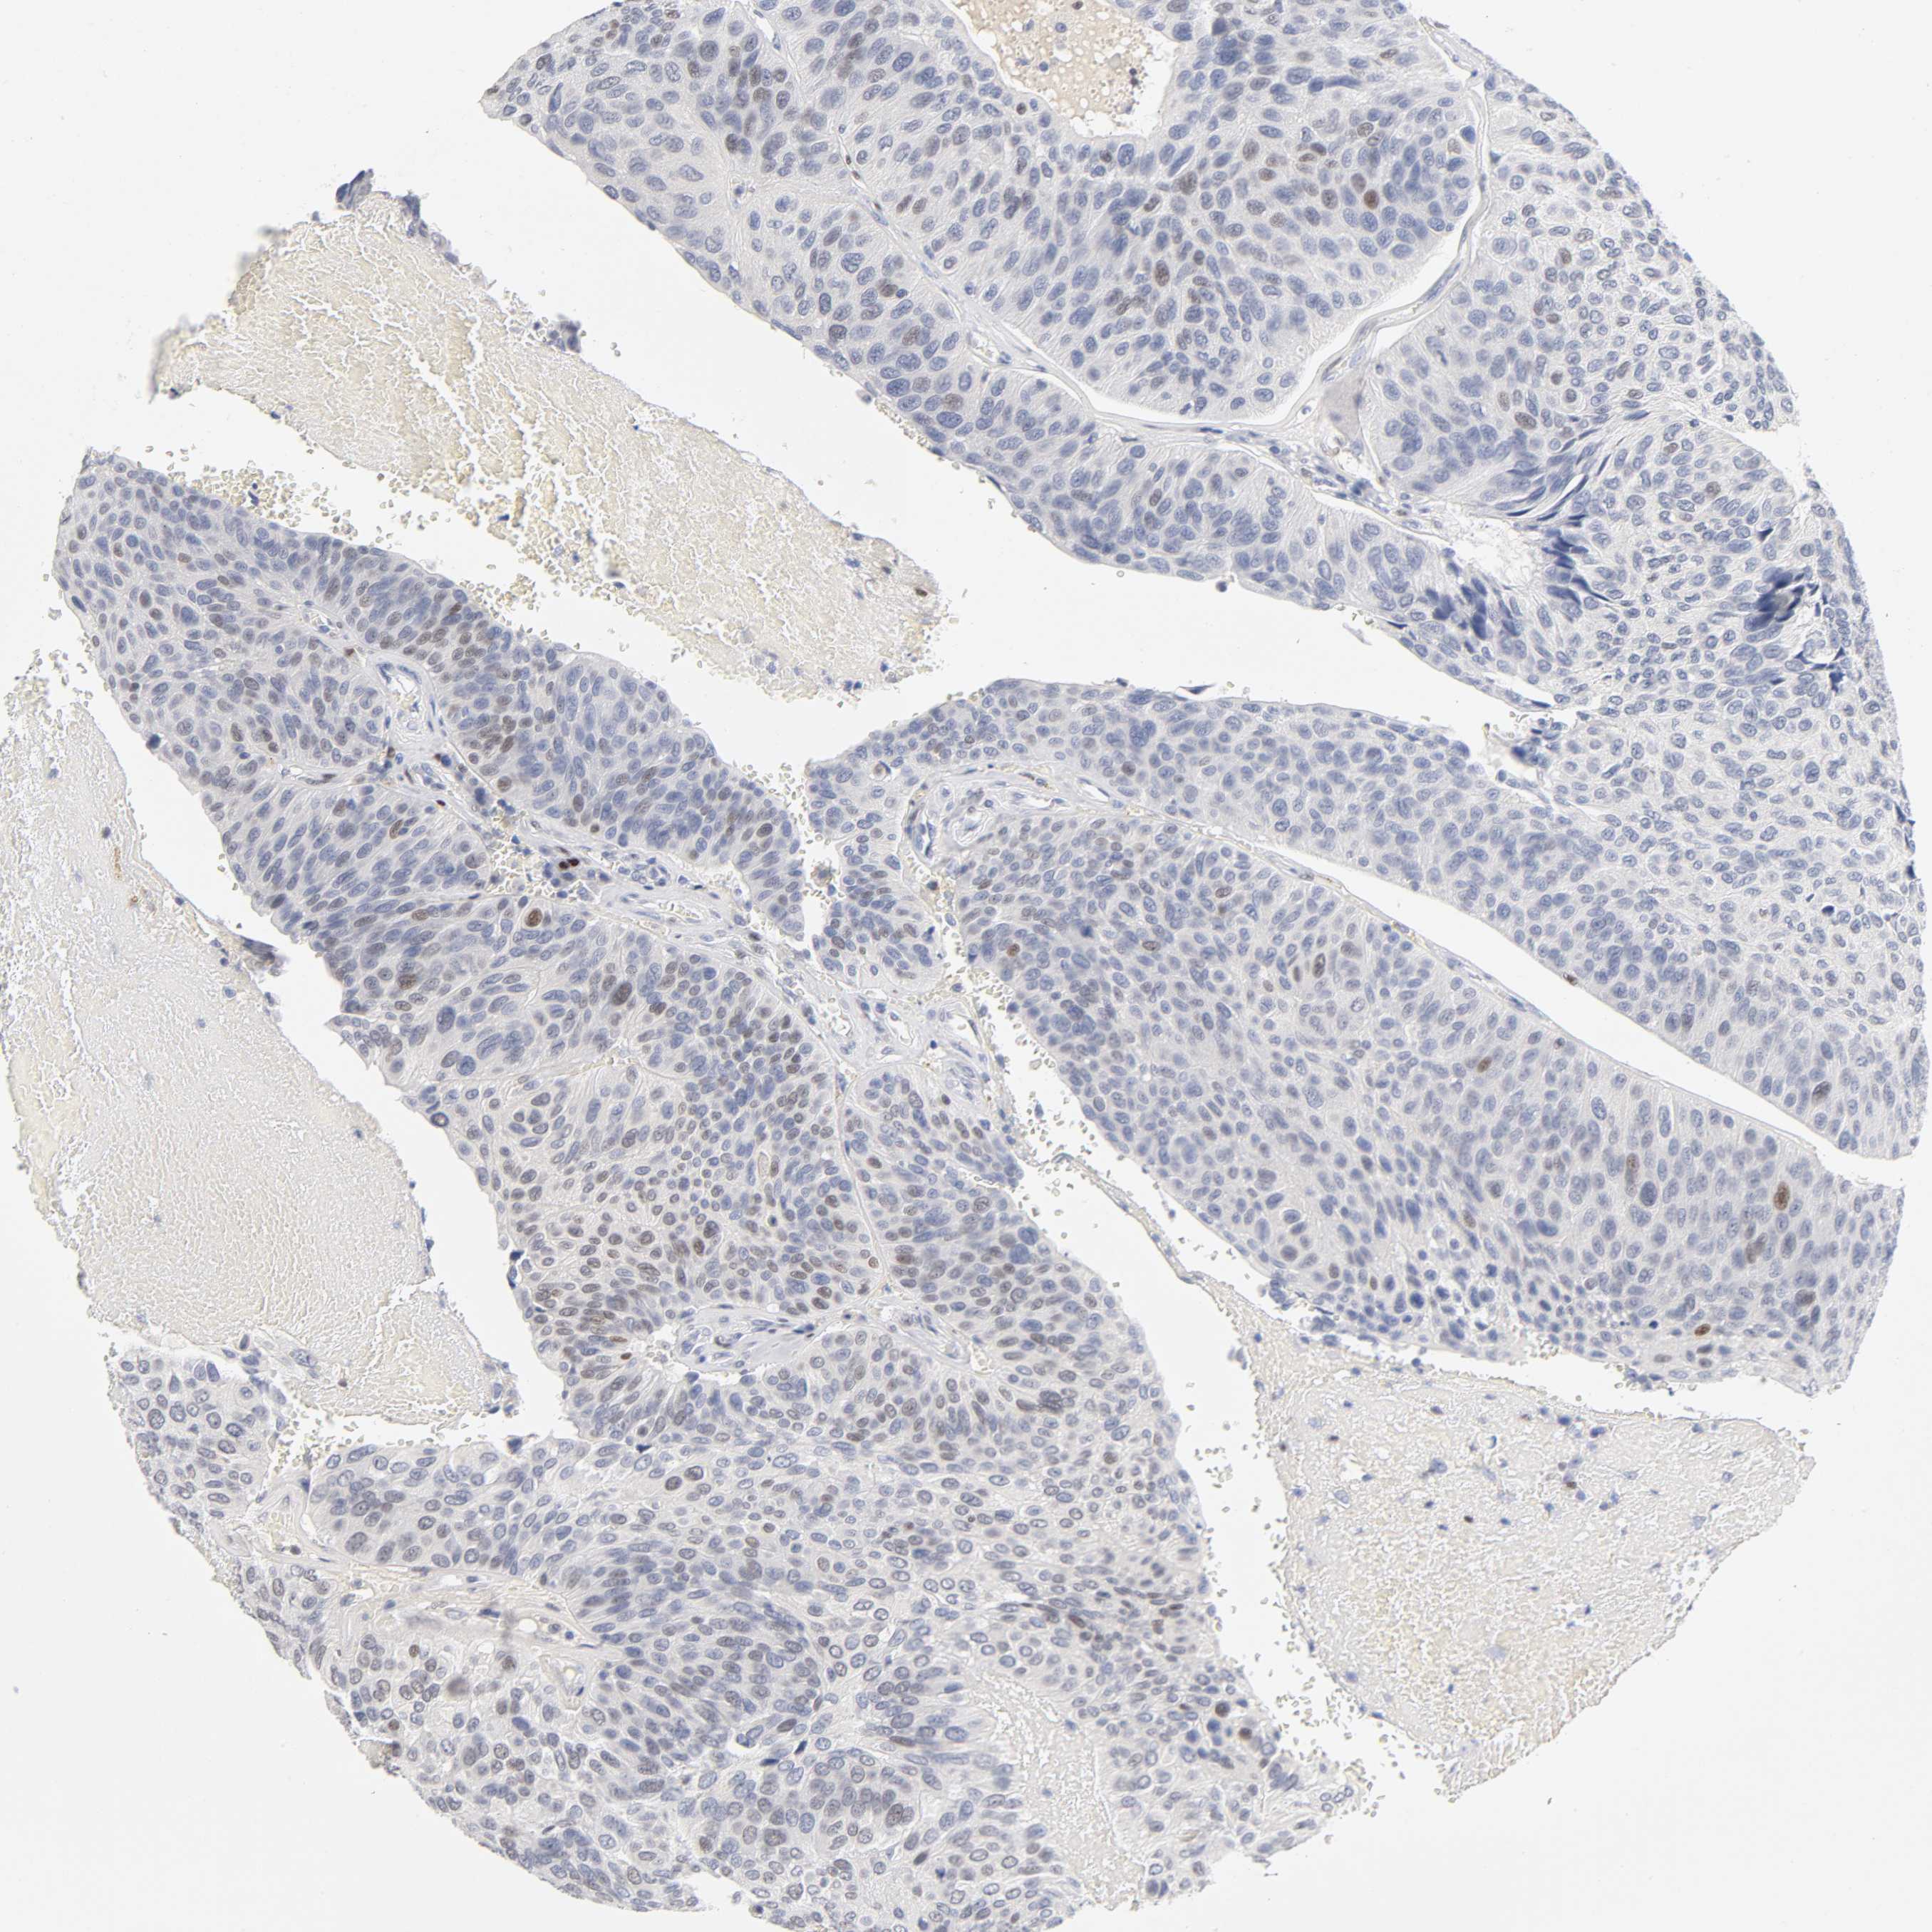

UROTHELIAL CANCER - Protein expressioni

A mouse-over function shows sample information and annotation data. Click on an image to view it in a full screen mode. Samples can be filtered based on level of antibody staining by selecting one or several of the following categories: high, medium, low and not detected. The assay and annotation is described here.

Note that samples used for immunohistochemistry by the Human Protein Atlas do not correspond to samples in the TCGA dataset.

Antibody stainingi

Antibody staining in the annotated cell types in the current human tissue is reported as not detected, low, medium, or high, based on conventional immunohistochemistry profiling in selected tissues. This score is based on the combination of the staining intensity and fraction of stained cells.

Each image is clickable and will lead to virtual microscopy that enables deeper exploration of all samples and also displays staining intensity scores, fraction scores and subcellular localization as well as patient and tissue information for each sample.

Antibody HPA032146

Antibody CAB004580

Staining

High

Medium

Low

Not detected

Intensity

Strong

Moderate

Weak

Negative

Quantity

>75%

75%-25%

<25%

None

Location

Nuclear

Cytoplasmic/membranous

Cytoplasmic/membranous,nuclear

Urothelial carcinoma, High grade

Urothelial carcinoma, Low grade

Urothelial carcinoma, NOS